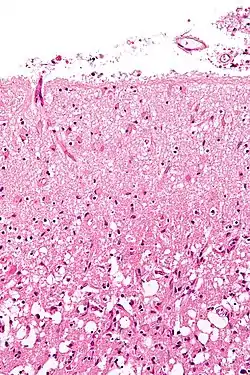

Intracerebral bleed

It generally occurs in small arteries or arterioles and is commonly due to hypertension,[49] intracranial vascular malformations (including cavernous angiomas or arteriovenous malformations), cerebral amyloid angiopathy, or infarcts into which secondary hemorrhage has occurred.[2] Other potential causes are trauma, bleeding disorders, amyloid angiopathy, illicit drug use (e.g., amphetamines or cocaine). The hematoma enlarges until pressure from surrounding tissue limits its growth, or until it decompresses by emptying into the ventricular system, CSF or the pial surface. A third of intracerebral bleed is into the brain's ventricles. ICH has a mortality rate of 44 percent after 30 days, higher than ischemic stroke or subarachnoid hemorrhage (which technically may also be classified as a type of stroke[2]).

Hemorrhagic

Hemorrhagic strokes are classified based on their underlying pathology. Some causes of hemorrhagic stroke are hypertensive hemorrhage, ruptured aneurysm, ruptured AV fistula, transformation of prior ischemic infarction, and drug-induced bleeding.[61] They result in tissue injury by causing compression of tissue from an expanding hematoma or hematomas. In addition, the pressure may lead to a loss of blood supply to affected tissue with resulting infarction, and the blood released by brain hemorrhage appears to have direct toxic effects on brain tissue and vasculature.[43][62] Inflammation contributes to the secondary brain injury after hemorrhage.[62]